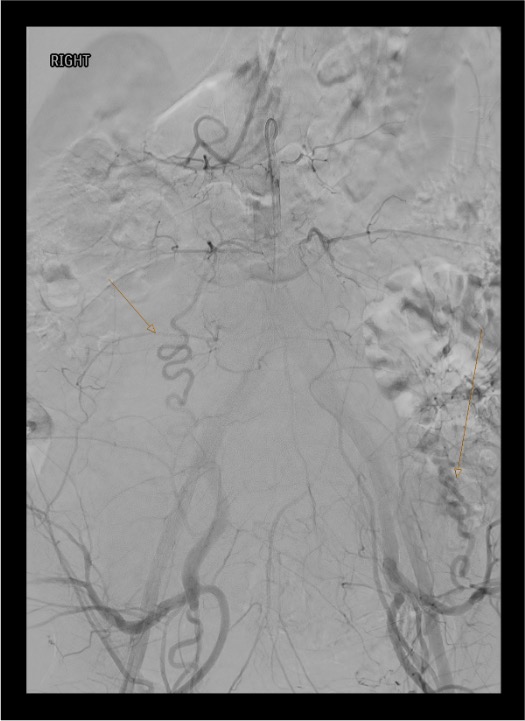

- Ovarian artery — arises from aorta; provides significant collateral supply to gravid/postpartum uterus; must check if bleeding persists after bilateral UAE

- Bilateral embolization almost always required — rich cross-pelvic collateralization means unilateral embolization is rarely sufficient for diffuse uterine bleeding / atony

Repeat selective right uterine artery catheterization with microcatheter past the cervicovaginal branch. Bilateral embolization is mandatory in diffuse atony — unilateral embolization has significantly higher failure rate in PPH.

Continued Hemorrhage Despite Bilateral Uterine Artery Embolization

Check for ovarian artery supply — hypertrophied ovarian arteries from the aorta can provide extensive blood supply to the postpartum uterus. Perform nonselective aortography to identify collaterals. Investigate cervicovaginal branches, internal pudendal artery, obturator artery, and round ligament artery (from inferior epigastric / external iliac). Remove vaginal or uterine packing temporarily to unmask angiographic abnormality. If anterior division embolization of IIA may be required when uterine artery cannot be selectively catheterized.